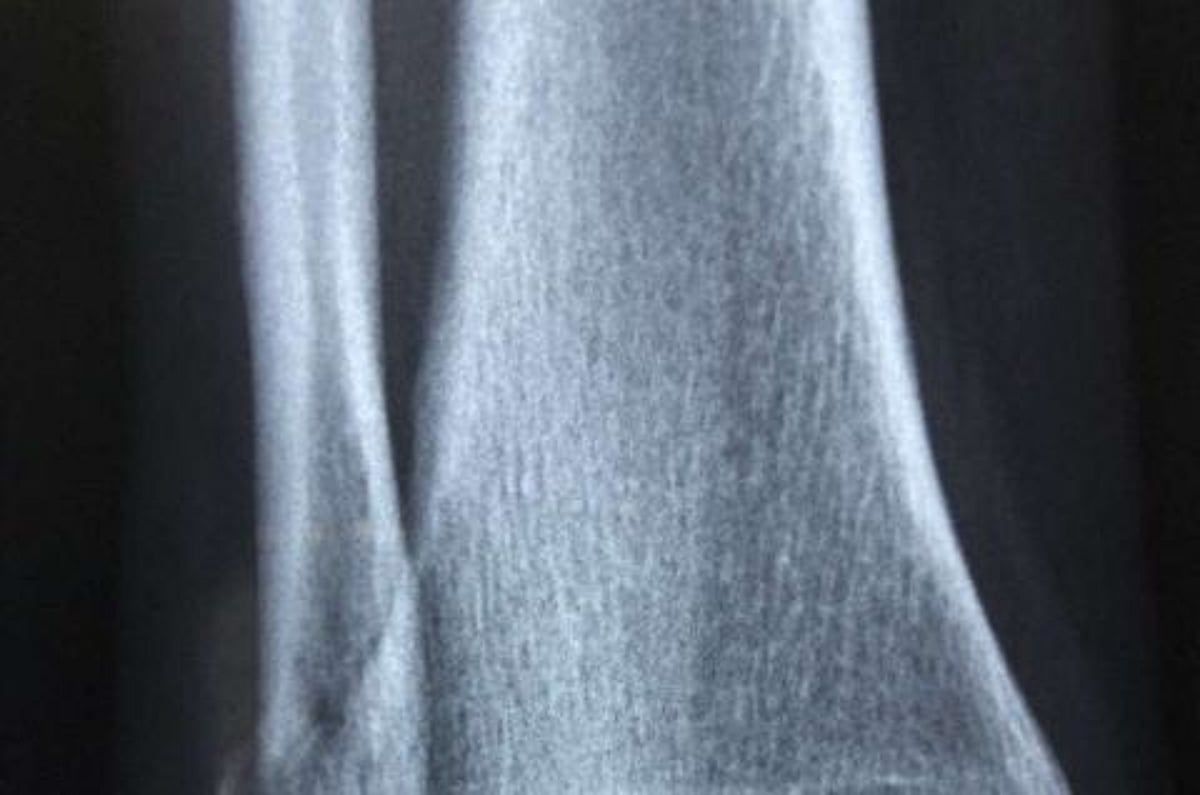

في اكتشافٍ هام، وجد باحثون في كلية الطب بجامعة جونز هوبكنز الأمريكية، أن دواءين مُسكّنين شائعي الاستخدام يُمكنهما إبطاء نمو وانتشار سرطان العظام لدى فئران التجارب. وتُشير الدراسة، التي نُشرت في دورية "وقائع الأكاديمية الوطنية للعلوم"، إلى إمكانية إعادة استخدام هذه الأدوية كاستراتيجية علاجية جديدة لساركوما العظام، وهو ورم خبيث في العظام.

أكد تحليل أنسجة ساركوما العظام البشرية وجود نفس التفاعل بين الأعصاب والورم لدى البشر. ويعتزم الباحثون مواصلة البحث في الآليات الدقيقة المعنية، على أمل تمهيد الطريق لتجارب بشرية مستقبلية.